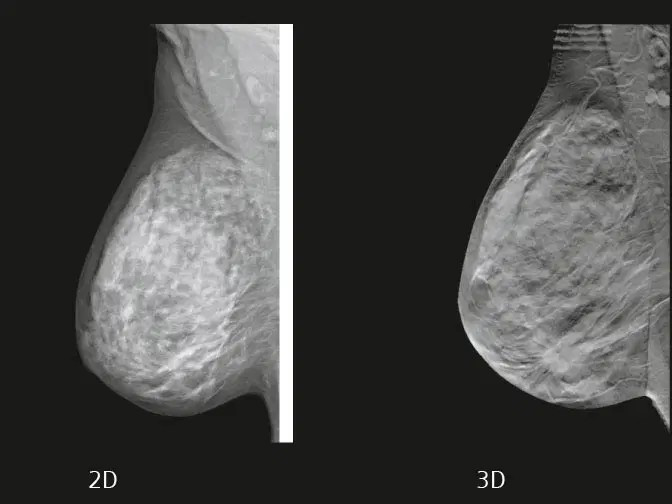

マンモグラフィは3D(トモシンセシス)を採用し隠れた腫瘍を見つけやすくなりました。